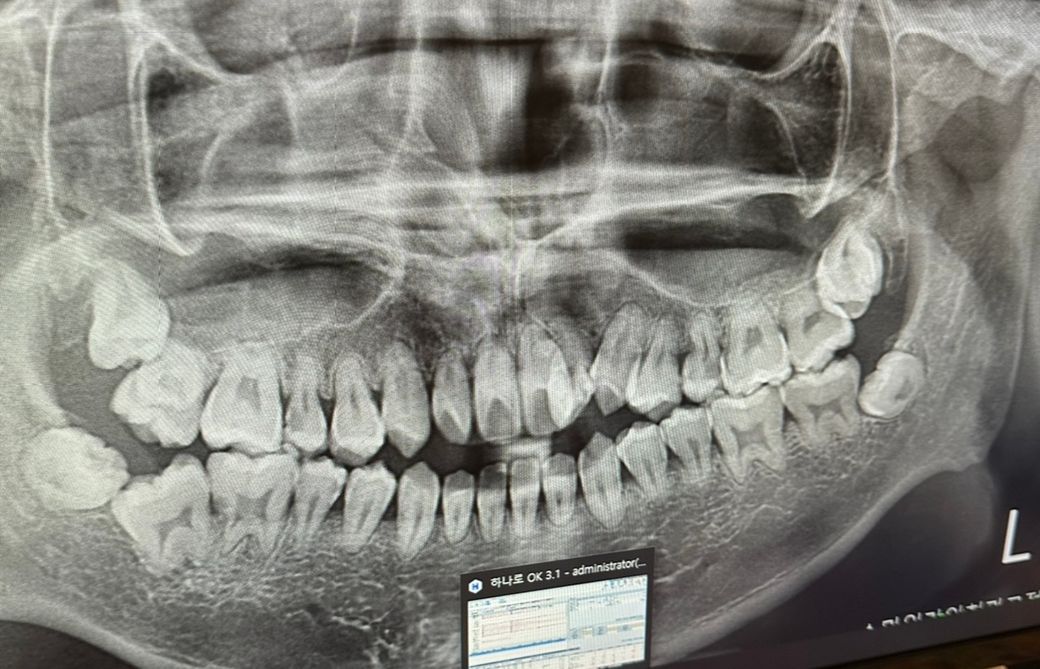

뿌리가 많이 짧은데 교정하기 힘들까요?

개방교합이랑 부정교합이 있어서 해야 하는데 위험 부담이 클거같아 걱정이네요 한곳에선 본인은 못하겠다고 큰 병원 가봐서 물어보라고 하긴 하는데 이게 큰 병원에서는 가능할까요.. 하면 어떤식으로 하나요 안된다고 하면 라미네이트나 그런식으로 보기 좋게 할수도 있을까요?

사진으로 보아 뿌리가 짧아 교정하면 치아가 흔들거리게 될 위험성이 높습니다. 아마도 큰병원도 어려울 가능성이 높아보입니다. 크라운으로 씌워 가지른하게 보지 좋게 하는 것도 한 방법입니다.

교정을 하게 되어 치아에 교정력이 가해지게 되면 치근흡수가 일어날수 있습니다.

또한 치아가 정출되는 과정에서 치아의 뿌리가 짧게 되면 쉽게 흔들리거나 약해 질수 있기때문에 교정을 신중하게 해야 할것으로 생각됩니다.

교정 부작용으로 치근흡수가 있는데 이미 뿌리가 다소 짧아보입니다 물론 사진상 왜곡이 있을 수도 있으나 이미 검사한 치과에서 뿌리가 짧다고 했다면 진짜로 짧은 것이고요 교정외 말씀하신 라미네이트, 크라운 등으로 치열개선하는 방법도 있겠습니다만 생니를 미용목적으로 갈아내는건 절대 추천하지 않습니다